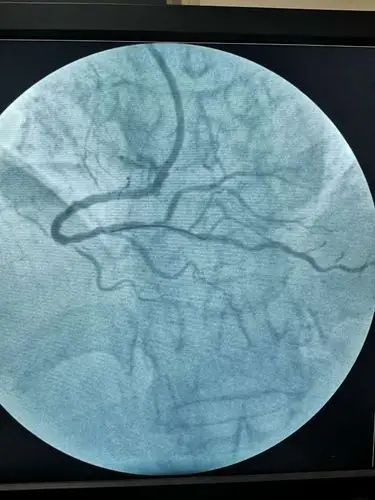

心脏冠状动脉造影

清晰的心脏冠脉造影图片!

冠脉造影术——叶县二院介入科

冠状动脉狭窄的血管造影